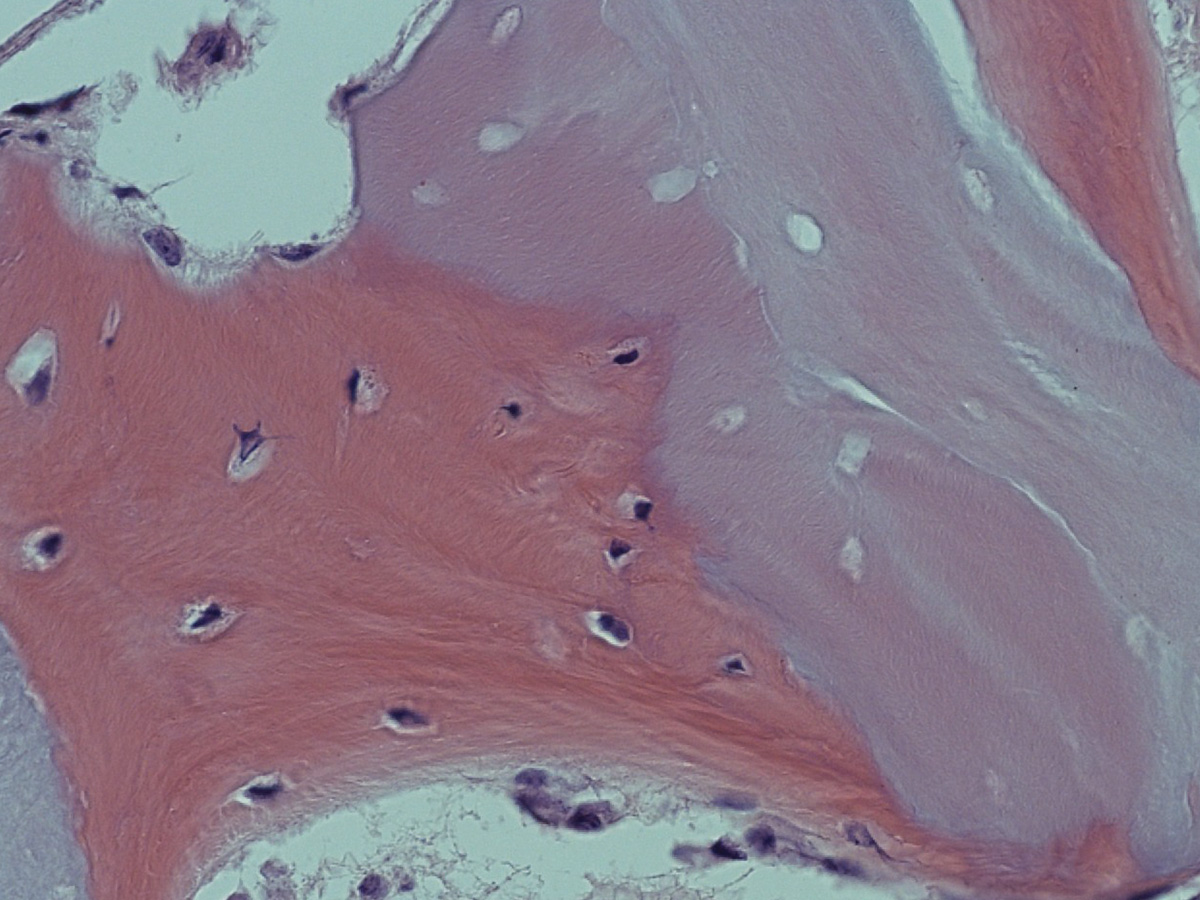

Abbildung 10

Abbildung 11

Histologie bei stärkerer Vergrößerung: In den Resorptionslakunen sind Osteozyten erkennbar.